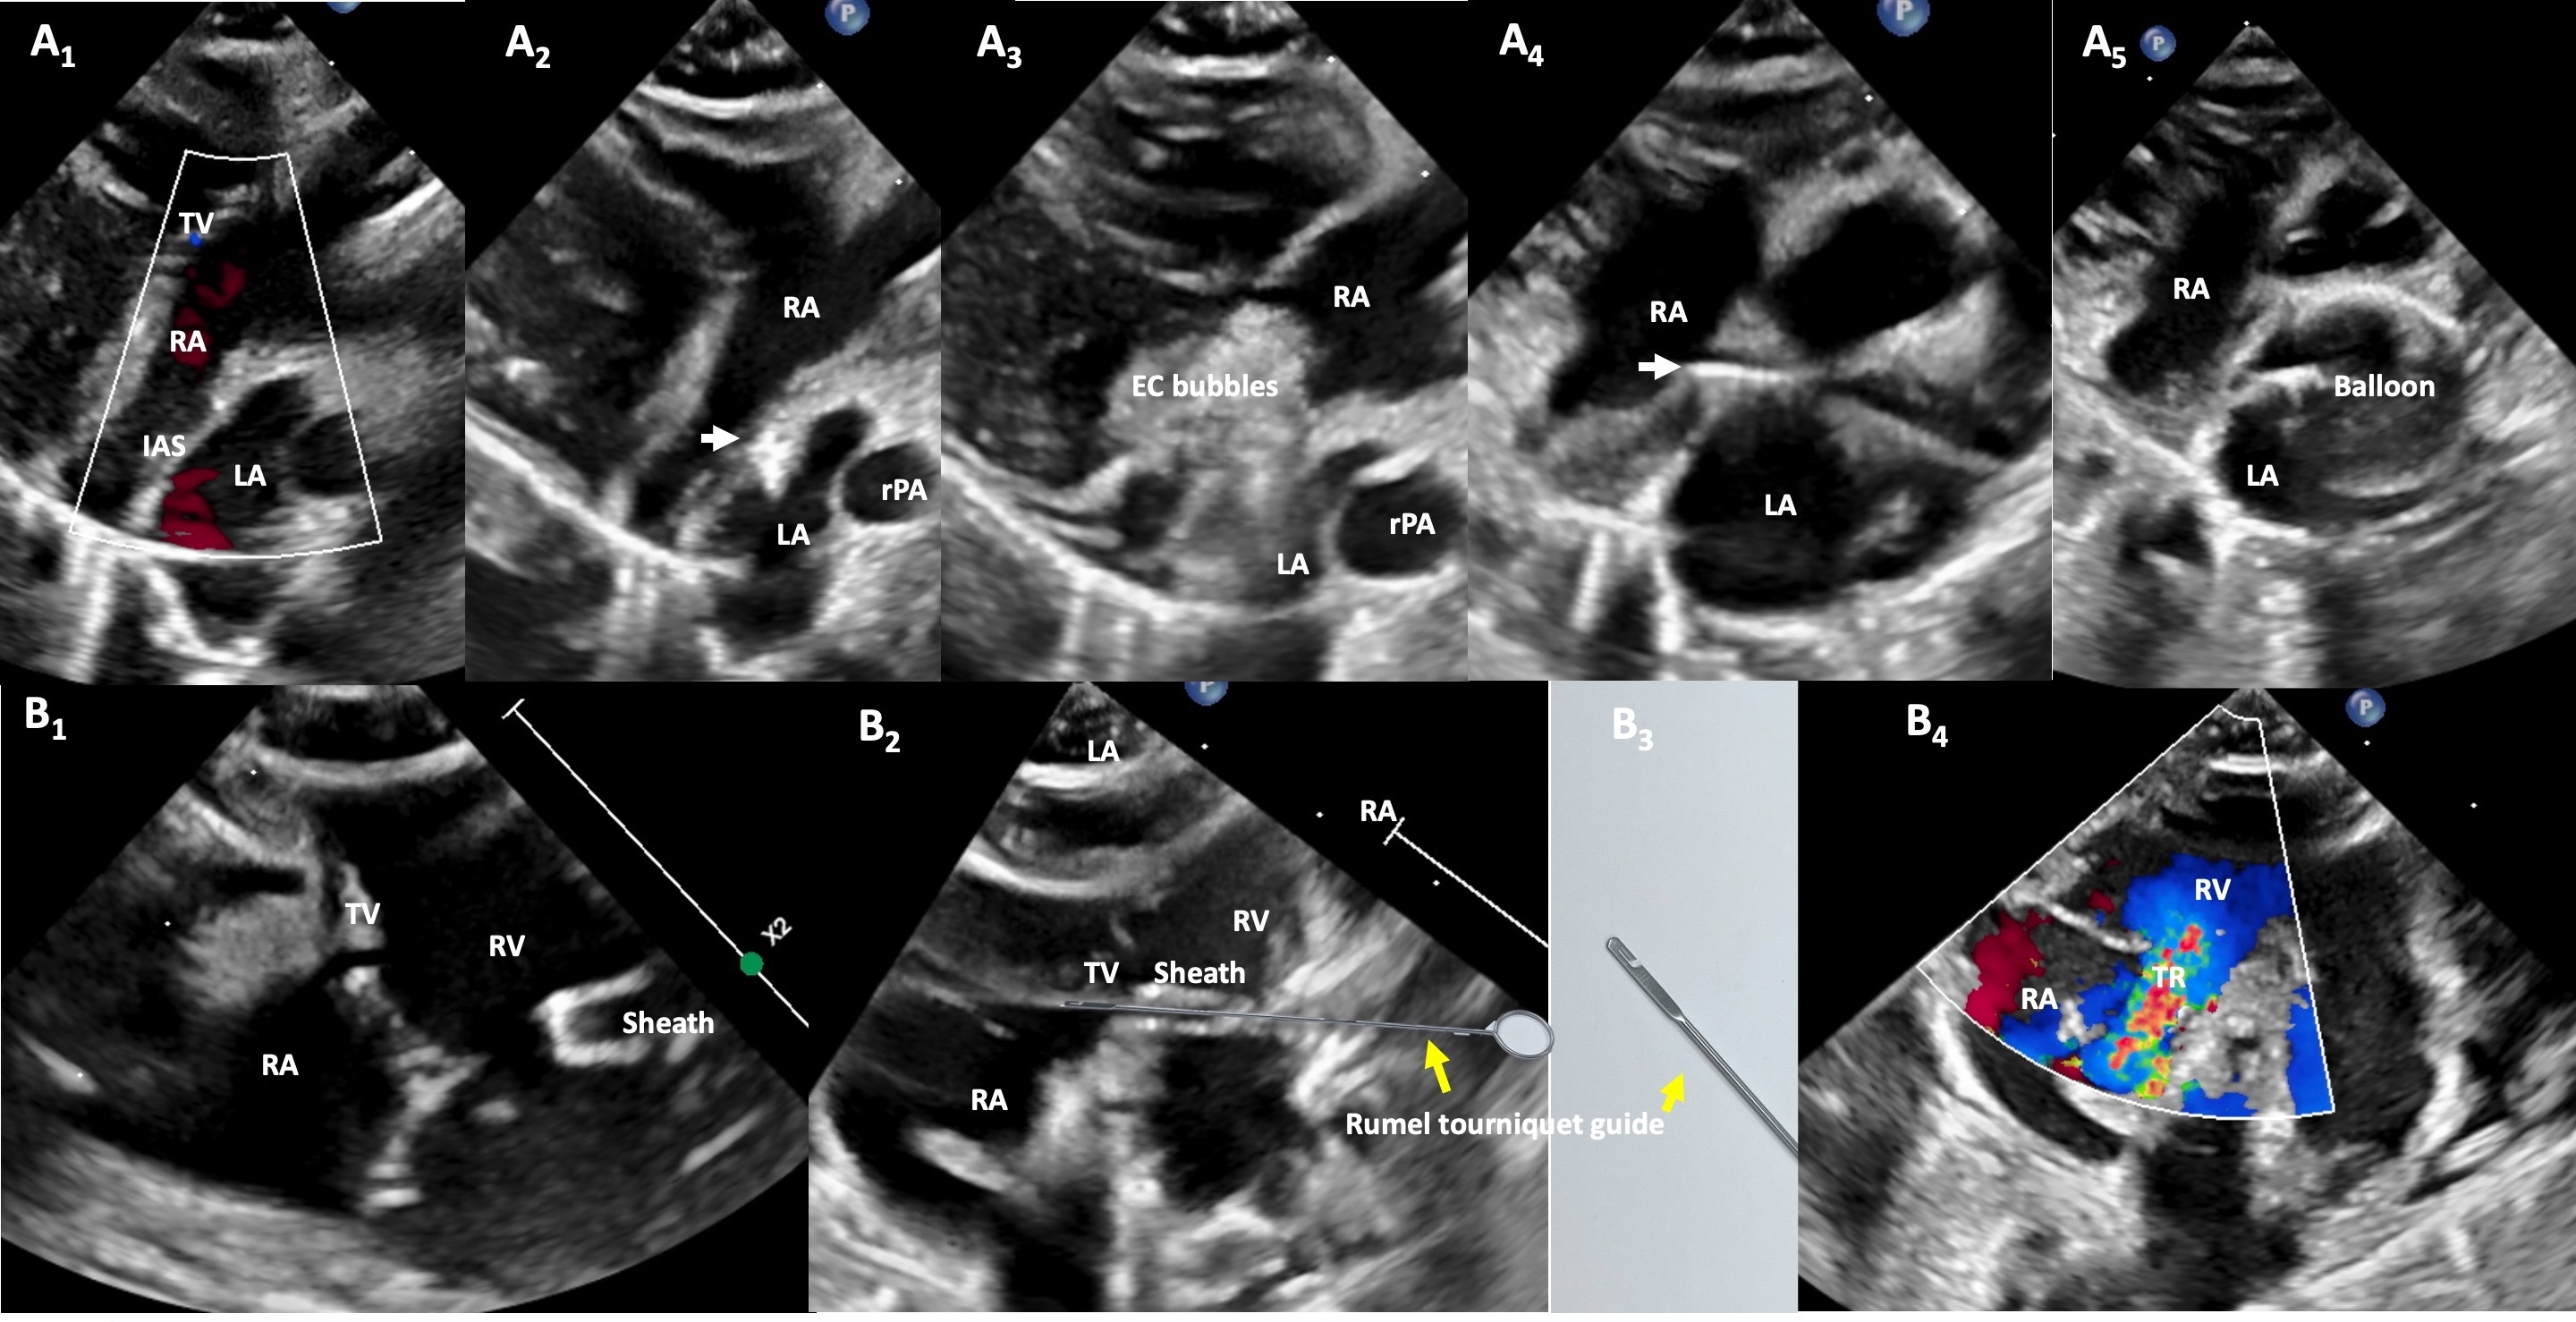

Neonatal pigs (n=8; weight 6.1±2.6 kgs) were used. A median sternotomy was performed. A 6-mm ring enforced PTFE graft was anastomosed end-side to the main pulmonary artery (MPA), end-end to the innominate artery and occluded with a vascular clamp. Under epicardial echocardiography guidance, the atrial septum was percutaneously perforated using electrocautery. (Figure 1A). Electrocautery was applied using a coaxial system of 4 Fr JR 3 catheter and a 0.014-inch coronary wire with its denuded tip at the atrial septum. Balloon atrial septostomy was performed using B. Braun Z-5 13.5 mm and/or the Edwards Miller septostomy balloon. To prevent RV distension, a per-ventricular Tricuspid valve (TV) avulsion was done using a Rumel tourniquet guide as a snare placed through a 7 Fr per-ventricular sheath (Figure 1B) . The systemic to pulmonary artery shunt (SPS) was unclamped, and antegrade pulmonary blood (APF) was interrupted by the occlusion of the MPA. Inotropic support was initiated. Donor pig blood was transfused for volume replacement. Hemodynamic and laboratory data were collected. The circulation was maintained for a minimum duration of 1 hour.